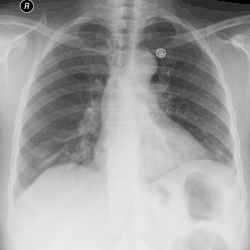

| Left tension pneumothorax with a large, well-demarcated area devoid of lung markings with tracheal deviation and movement of the heart away from the affected side. |

Tension pneumothorax

Tension pneumothorax is an emergent condition in which air gets trapped in the space between the chest wall and the lung. This space is referred to as the pleural space. Because air can't escape from this space, the air pocket grows larger and larger, resulting in the lung collapse closest to the pneumothorax. Forces are transmitted to the mediastinum and effectively "push" the mediastinal structures to the opposite side of the chest.[5]